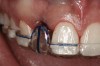

Figure 4  Characterization of the interproximal bone and tooth contacts: A periapical radiograph assists in measuring the distance from bone crest to the adjacent tooth contact points for missing tooth No. 8. The mesial bone crest to the adjacent tooth contact distance is < 5 mm, while the distal bone crest to adjacent tooth contact distance is > 6 mm (Fig 4). One-year following implant placement, conservation of these dimensions is revealed (Fig 5). The clinical photograph (Fig 6) of the lateral incisor adjacent to tooth No. 8 implant crown demonstrates that the absence of distal interproximal (papilla) fill related to the observed bone crest to contact distance exceeds 6 mm.

Figure 4

Figure 5  Characterization of the interproximal bone and tooth contacts: A periapical radiograph assists in measuring the distance from bone crest to the adjacent tooth contact points for missing tooth No. 8. The mesial bone crest to the adjacent tooth contact distance is < 5 mm, while the distal bone crest to adjacent tooth contact distance is > 6 mm (Fig 4). One-year following implant placement, conservation of these dimensions is revealed (Fig 5). The clinical photograph (Fig 6) of the lateral incisor adjacent to tooth No. 8 implant crown demonstrates that the absence of distal interproximal (papilla) fill related to the observed bone crest to contact distance exceeds 6 mm.

Figure 5

Figure 6  Characterization of the interproximal bone and tooth contacts: A periapical radiograph assists in measuring the distance from bone crest to the adjacent tooth contact points for missing tooth No. 8. The mesial bone crest to the adjacent tooth contact distance is < 5 mm, while the distal bone crest to adjacent tooth contact distance is > 6 mm (Fig 4). One-year following implant placement, conservation of these dimensions is revealed (Fig 5). The clinical photograph (Fig 6) of the lateral incisor adjacent to tooth No. 8 implant crown demonstrates that the absence of distal interproximal (papilla) fill related to the observed bone crest to contact distance exceeds 6 mm.

Figure 6